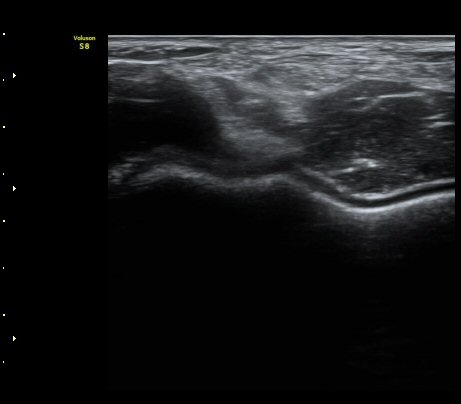

À̵ιڱ٠ÈûÁÙ Á¾´Ü¸é°Ë»ç¿¡¼­ ÈûÁÙÀÌ Àú¿¡ÄÚ°í °üÂûµÇ°í ÈûÁÙ ÁÖº¯ÀÇ ¼ö¾×Àú·ù°¡

¾Ö¸ÅÇÏ°Ô °üÂûµÈ´Ù(±×¸² 7). ŽÃËÀÚ ±ÙÀ§ºÎ¸¦ ÇǺÎÂÊÀ¸·Î ´©¸£´Ï ÈûÁÙÀÌ °í¿¡ÄÚ·Î

°üÂûµÇ°í ¼ö¾×Àú·ùµµ ¶Ñ·ÈÇÏ´Ù(±×¸² 8).